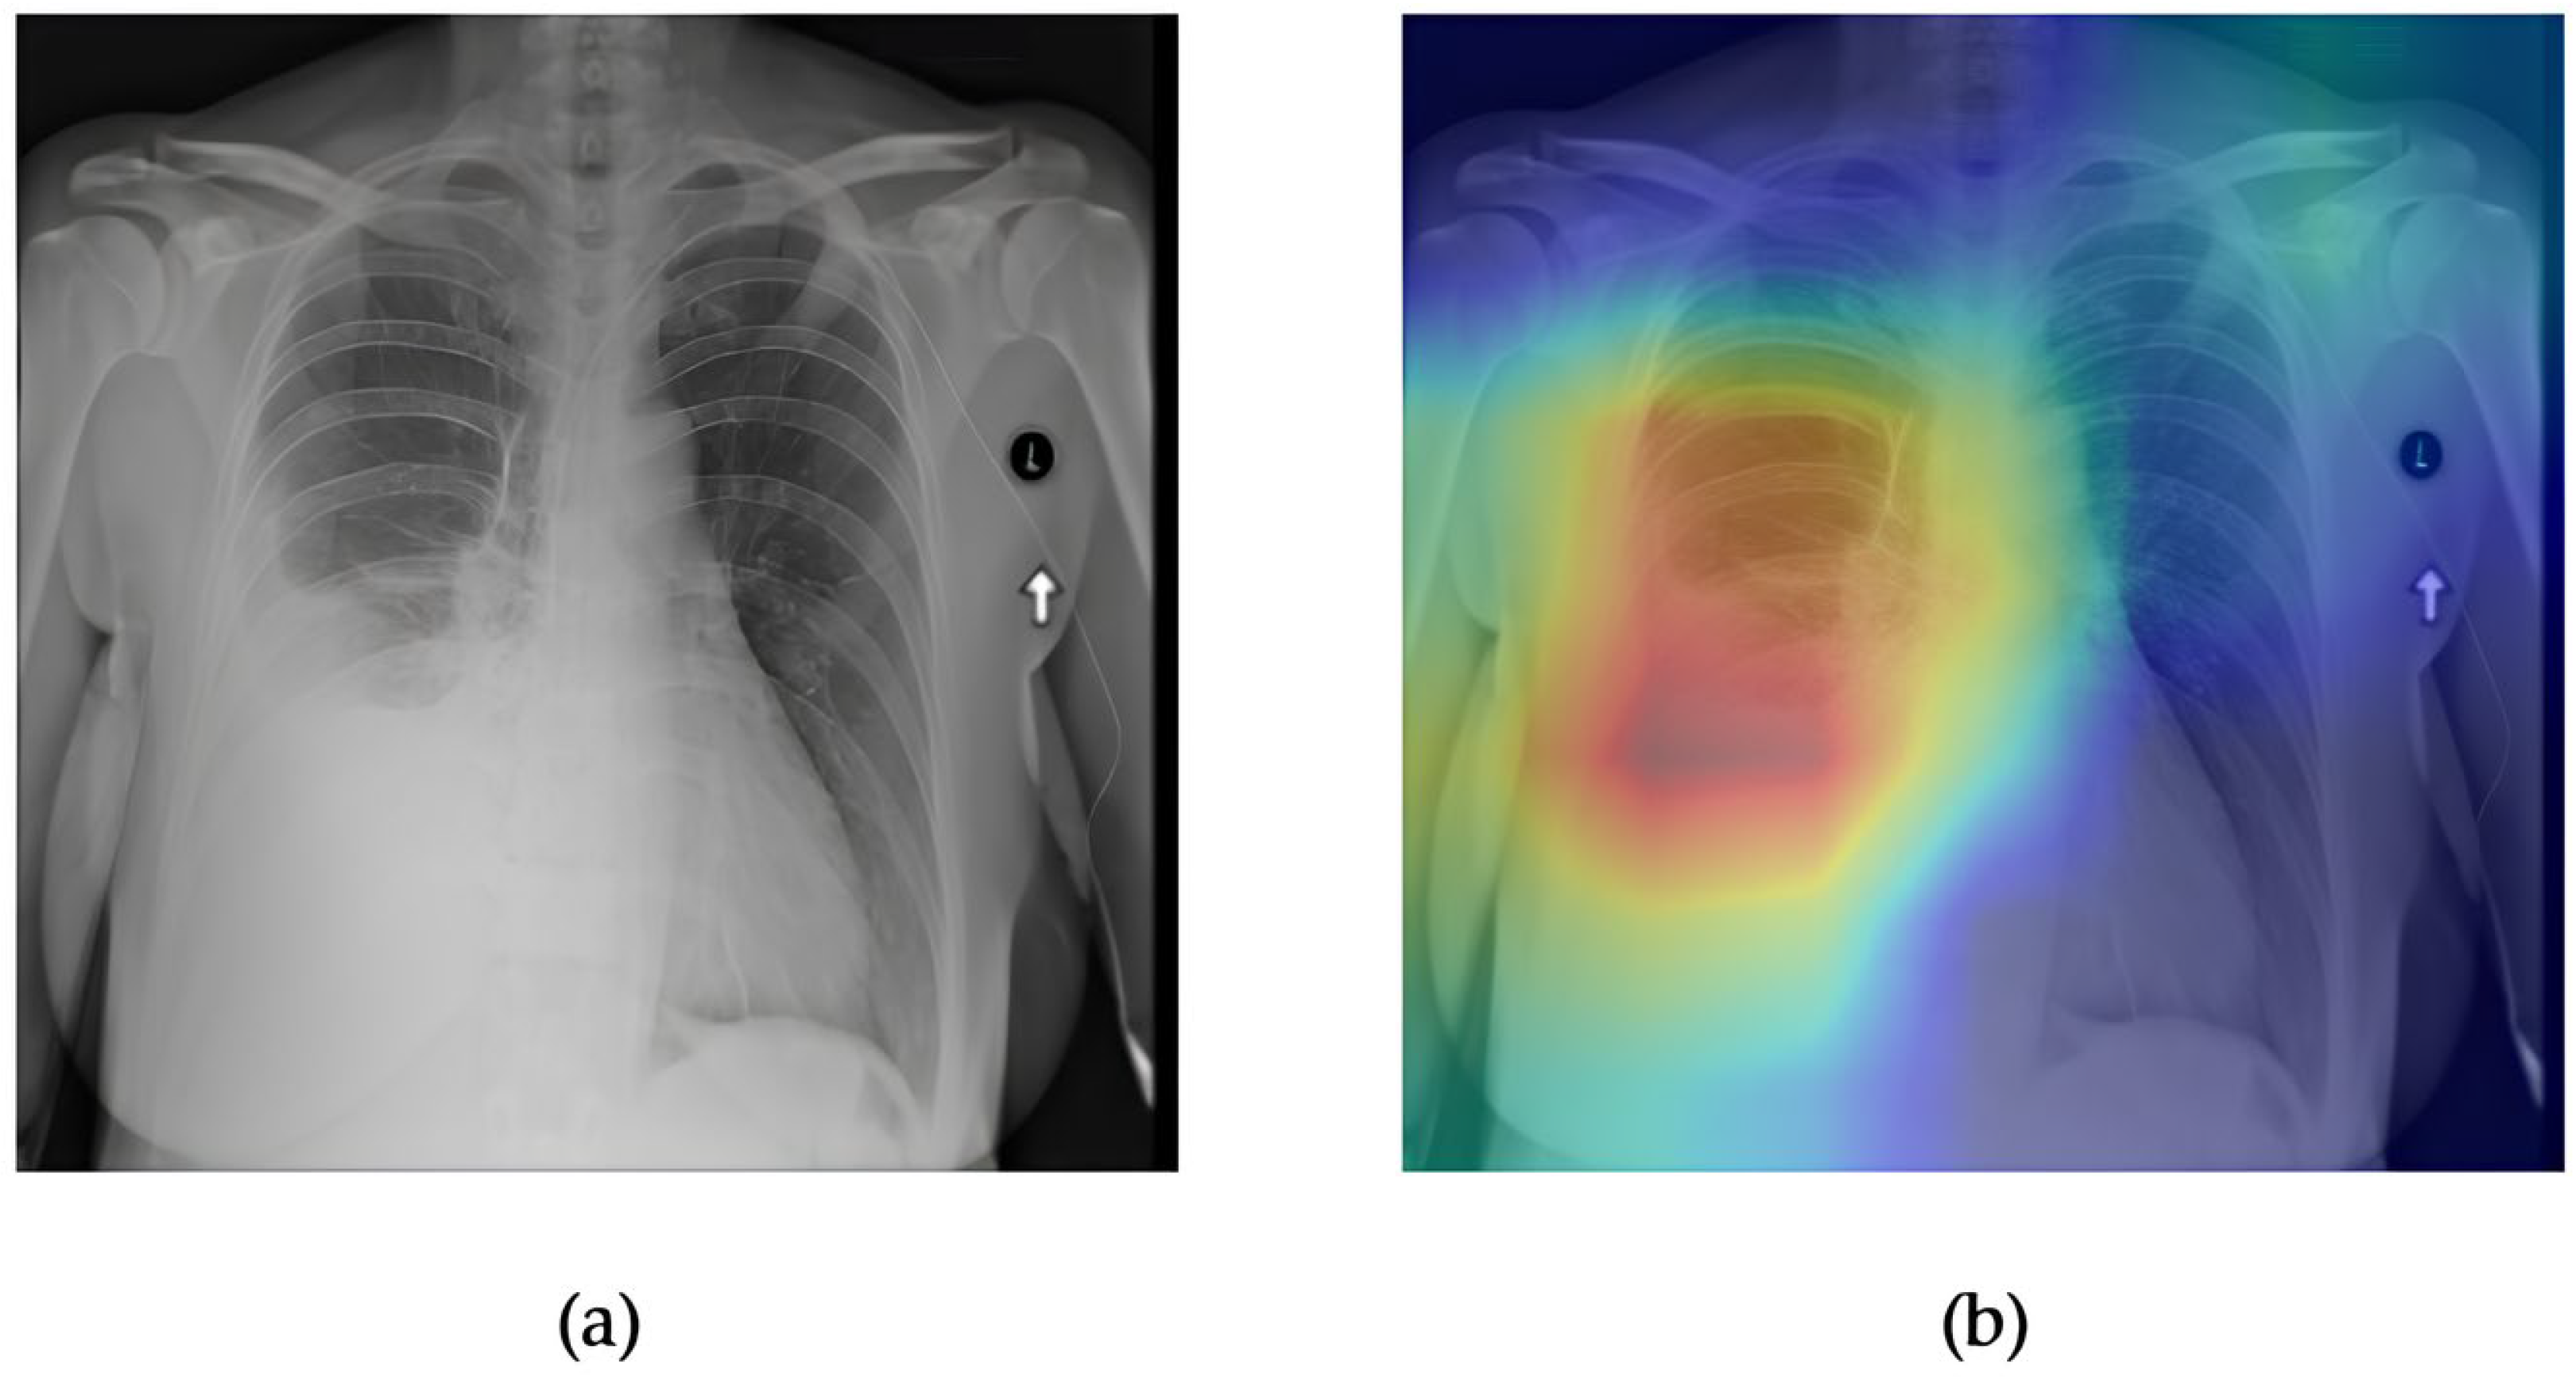

- Although our Grad-CAM-based explainability provides useful localization cues, it is inherently limited by its post hoc nature and reliance on gradient flow from the final convolutional layers. Future research could incorporate advanced interpretability techniques such as Layer-wise Relevance Propagation (LRP), Integrated Gradients, or attention rollouts in Transformers, which may offer a more complete understanding of model reasoning.